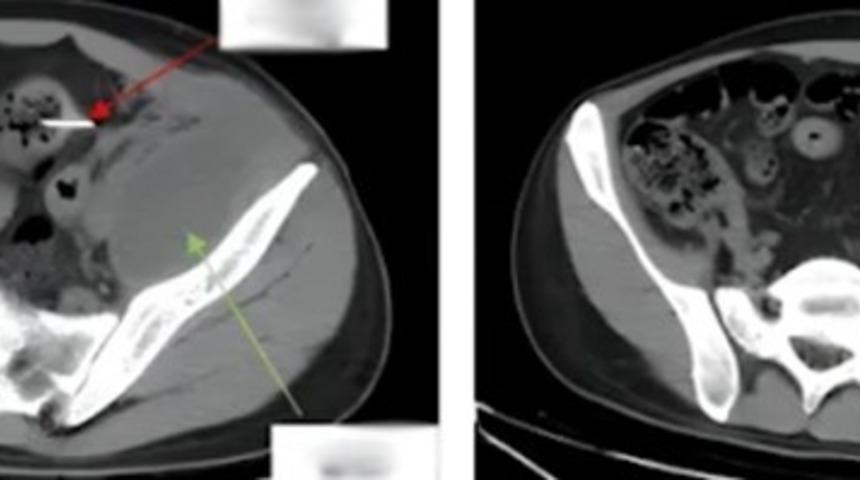

Hastanede röntgen çekildikten sonra sol karın boşluğunun bağırsak duvarında sivri uçlu yabancı bir cisim tespit edildi. Bu cismin iltihaplanmaya ve bağırsak delinmesine neden olduğu ortaya çıktı. Uzun süredir devam eden enfeksiyon 180 mililitre irin üretmişti, bu yüzden doktorlar 2 saat 40 dakika süren laparoskopik bir ameliyat gerçekleştirdiler ve yabancı cismi çıkartmayı başardılar.

Yabancı cismin 13 cm uzunluğunda çöp şiş olduğu tespit edilirken 28 yaşındaki hasta ameliyattan iki gün sonra yeniden yürüyebildi. 5 gün sonra hastanede daha rahat hareket edebildi. 16 gün sonra hastaneden taburcu edildi.